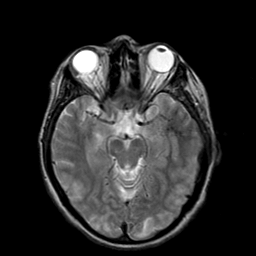

Hypertensive Encephalopathy, overlay -- Slice #9

[Home][Help][Clinical] Slice 9